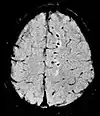

| Diffusion weighted (DWI) | Conventional | DWI | Measure of Brownian motion of water molecules[24]. | High signal within minutes of cerebral infarction (pictured)[25]. | ![]() |

| Apparent diffusion coefficient | ADC | Reduced T2 weighting by taking multiple conventional DWI images with different DWI weighting, and the change corresponds to diffusion[26]. | Low signal minutes after cerebral infarction (pictured)[27]. | ![]() | |